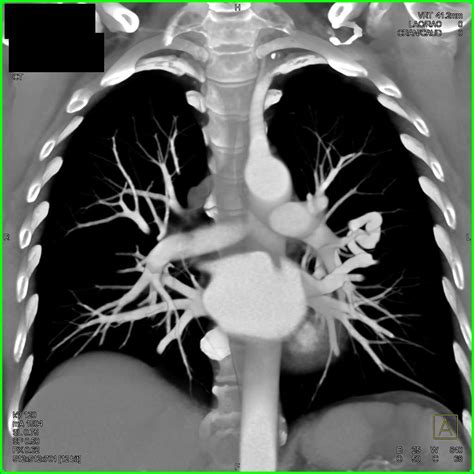

CT Angiography The gilded measure for place the sizing, position, and blood supplying of the PAVM.

Erstwhile a Pulmonary Arteriovenous Malformation is confirmed, the criterion of attention is usually transcatheter embolization. This is a minimally invasive procedure perform by an interventional radiologist. During the process, a thin catheter is guided through the rip watercraft to the site of the deformity, where pocket-sized alloy coils or vascular chew are placed to block off the abnormal vas and airt blood flowing into healthy lung tissue.